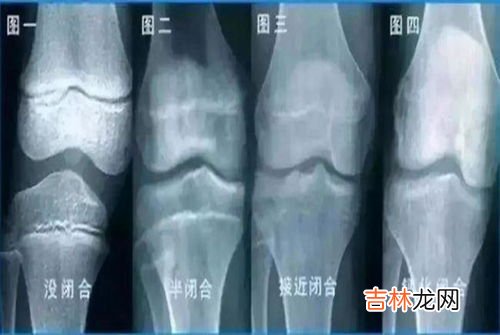

3、打了生长激素可以帮助长个子吗?打生长激素能否长高,是依据患者骨骺线是否闭合而定的 。生长激素是人体生长的一种重要的激素,它是由大脑垂体前叶生长激素细胞分泌的一种肽类激素,是体内最重要的促进生长的激素;生长激素 , 从出生后就开始分泌,使孩子身体长高,随着各年龄的增加,生长激素逐渐减少;如果生长激素正常分泌,能够促进神经以外的所有其他组织生长,能够促进体内代谢和蛋白质合成,能够刺激骨关节软骨和骨骺软骨生长 , 只要在骨骺线没有闭合的情况下,打生长激素是能够起到长高效果的 。

因此,在出现身材矮小的患儿,建议尽早的在医院进行检查,是否是由于生长激素缺乏导致,如果身材矮小的患儿是生长激素缺乏导致的,要在骨骺线闭合之前进行注射生长素,能够起到长高作用的,一般每年可长高8到12厘米 。但是随着骨龄的增大,骨骺线逐渐闭合,这时再打生长素,效果欠佳;如果骨骺线完全闭合,打生长激素是起不到长高效果的 。

骨骺闭合前使用生长激素是可以改善身高的,生长激素是临床治疗矮身材最安全有效的方法 。